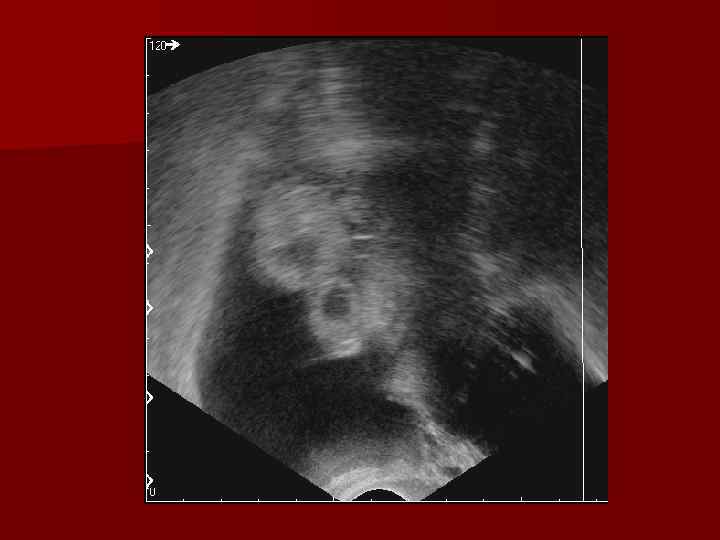

Синдром поликистозных яичников